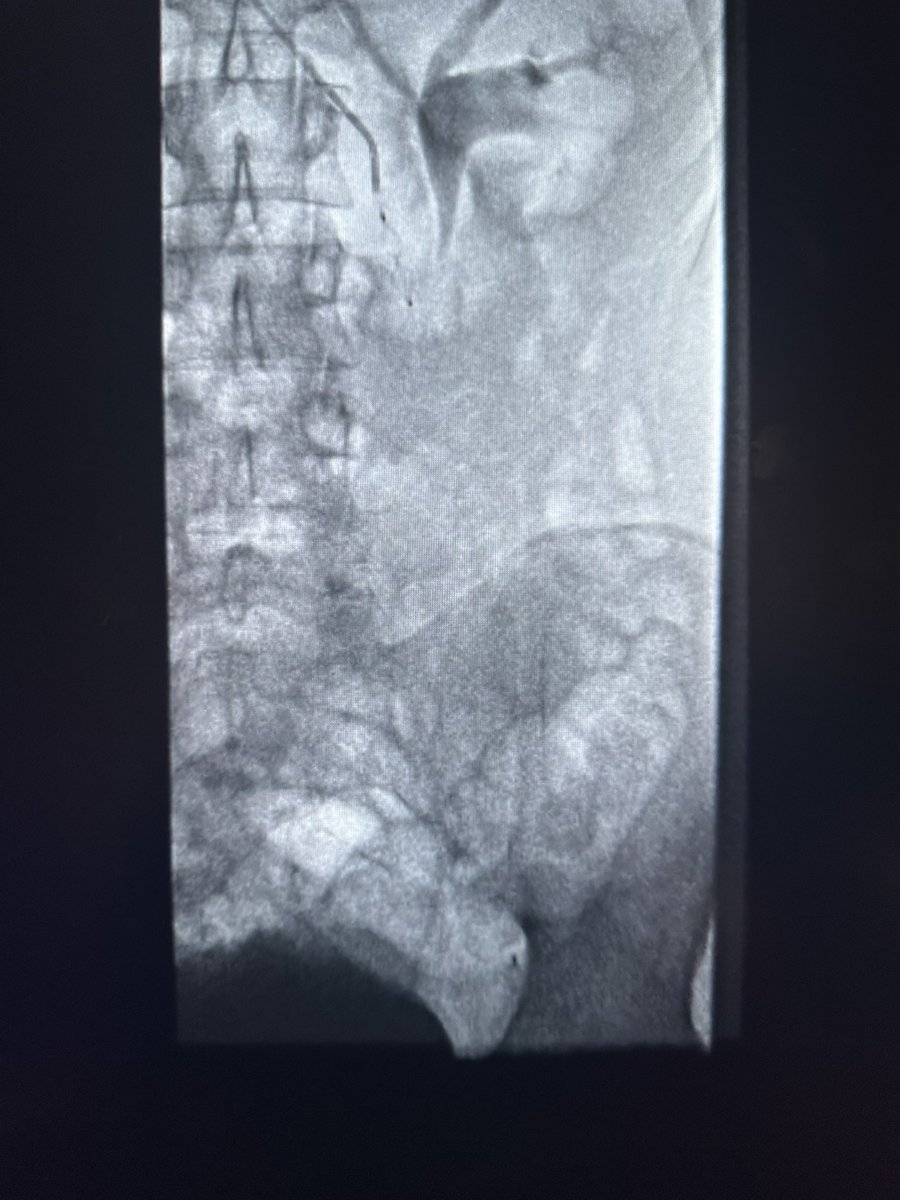

حالة من حالات نقص التروية الدموية الحاد مع وجود جرح غير ملتئم في القدم تم علاجها في وحدة #الأشعة_التداخلية بجامعة الملك سعود بالدخول من شرايين الفخذ والكاحل و إعادة فتح و توسيع الشرايين @ksumedicalcity @_KSU

د.سلطان رباح الحربي | Dr. Sultan R.Alharbi tweet mediaد.سلطان رباح الحربي | Dr. Sultan R.Alharbi tweet mediaد.سلطان رباح الحربي | Dr. Sultan R.Alharbi tweet mediaد.سلطان رباح الحربي | Dr. Sultan R.Alharbi tweet media

في وحدة #الأشعة_التداخلية بجامعة الملك سعود نقوم بتوفير أحدث التقنيات لعلاج القدم السكرية ونقص التروية. الدخول للشرايين يتم من الفخذ ، أو في بعض الحالات المتقدمة من الكاحل أو حتى من اخر القدم. بعض التقنيات لا توجد الا في أماكن قليلة جداً بالشرق الأوسط @ksumedicalcity @_KSU @ksu_medicine @FcmKsu